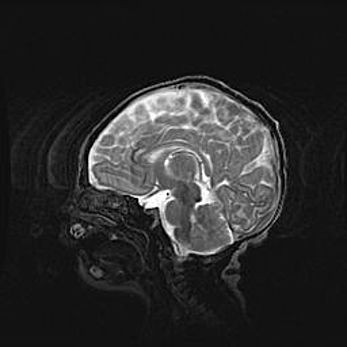

Неполная лизэнцефалия (пахигирия). Открытая гидроцефалия.

Возраст: 17 дней

Вес: 3110 г

Пол: мужской

Окружность головы: 33,5 см

Срок гестации: 35-36 недель

Лизэнцефалия—недоразвитие корковой пластинки и мозговых извилин в результате нарушения миграции нейронов коры. Поверхность мозговых полушарий гладкая. Микроскопически выявляется отсутствие нормальных слоев коры и скопление групп нейронов в подкорковом белом веществе.

Пахигирия—уменьшение числа вторичных извилин. В пораженном полушарии нервные клетки образуют толстый недифференцированный слой с неправильно расположенными нервными волокнами и группами гетеротопных клеток. Нервные клетки незрелые. Белое вещество истончено. При этом нередко аномально развит корково-спинномозговой путь.